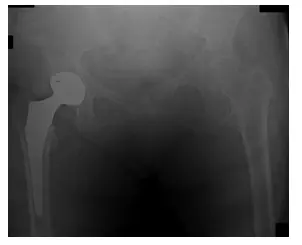

El paciente es un varón de 55 años que acudió quejándose de dolor bilateral en la cadera que, según declaró, había ido en aumento durante los últimos meses. El paciente acudió con radiografías para revisar, que indicaban que tenía artritis bilateral de las...